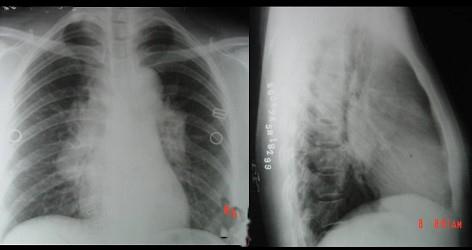

问题 男性,45岁,确诊结节病,胸部X线示肺部弥漫性病变不伴有肺门淋巴结增大,见图应属 ( )

选项 A.结节病0期 B.结节病Ⅰ期 C.结节病Ⅱ期 D.结节病Ⅲ期 E.结节病Ⅳ期

答案 D